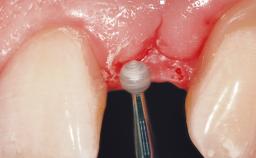

Immediate Placement of an Implant in a Maxillary Left Central Incisor Site

A 33-year-old female patient presented with an upper left central incisor that required extraction after a failed endodontic therapy. The tooth had been traumatized when the patient was a teenager and had undergone several endodontic treatments, including two apicectomy procedures. The patient was in good health and did not smoke. Clinical examination showed that the patient had a high lip line. In full smile, the gingival margins of the upper teeth were visible to the first molars. The gingival margins of central incisors 11 and 21 were only just showing. Examination of tooth 21 confirmed that the tooth was mobile and had hypererupted by 1 mm.

Soft Tissue Grafting Simultaneous

Soft Tissue Contour and Volume Slightly compromised